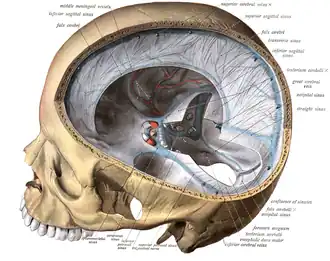

| Dural veins | |

Pathogenesis

The veins of the brain, both the superficial veins and the deep venous system, empty into the dural venous sinuses, which carry blood back to the jugular vein and thence to the heart. In cerebral venous thrombosis, blood clots usually form both in the veins of the brain and the venous sinuses. The thrombosis of the veins themselves causes venous infarction (damage to brain tissue due to a congested and therefore insufficient blood supply). This results in cerebral edema (both vasogenic and cytotoxic edema), and leads to small petechial haemorrhages that may merge into large haematomas. Thrombosis of the sinuses is the main mechanism behind the increase in intracranial pressure due to decreased resorption of cerebrospinal fluid (CSF). The condition does not typically lead to hydrocephalus, however, because there is no difference in pressure between various parts of the brain.[3] However, those who have deep cerebral venous sinus thrombosis or oedema at basal ganglia are more prone to hydrocephalus development.[13]

Central venous thromboses usually involve the dural sinuses with or without involvement of the cortical veins; isolated cortical venous thromboses are extremely rare with only about 100 cases reported.[6]